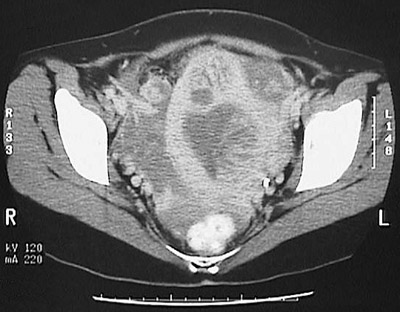

This abdominal CT scan view of the pelvis demonstrates a solid and cystic mass in the region of the uterus extending into the pelvis which is consistent with a choriocarcinoma.